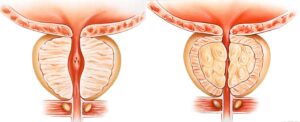

Hiperplasia Prostática Benigna: Tratamento por Cirurgia Robótica

A Hiperplasia Prostática Benigna (HPB) é uma condição comum que afeta muitos homens à medida que envelhecem. Caracterizada pelo aumento não canceroso da próstata, a HPB pode causar sintomas incômodos